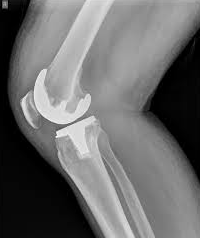

The Future of Joint Replacement Surgeries in Ja...